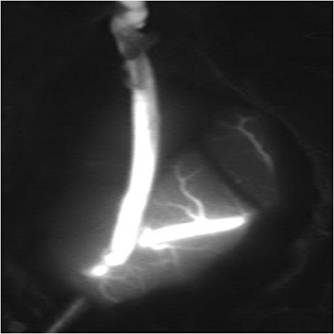

外六科吴杰主任、闫学强主治医生对患者进行了综合评估:患者3个月前为左侧脑室出血,且目前左侧半球供血不足比右侧显著,医生拟先实施左侧脑内血管重建术,二期实施右侧脑内血管重建术。几日后,患者在全麻下接受左侧颞浅动脉-大脑中动脉搭桥术,医生采取左侧额颞直切口,长约175px,创伤小(术中如图4);术中医生利用荧光造影,可清晰见到吻合血管通畅(如图5)。整个手术过程顺利,患者术后恢复良好,复查DSA,吻合血管通畅,颅内血供明显改善(如图6),并无神经功能缺失。目前患者已痊愈出院。

图5,术中荧光造影显示吻合血管通畅良好

图6,术后复查DSA,吻合血管通畅,颅内供血改善